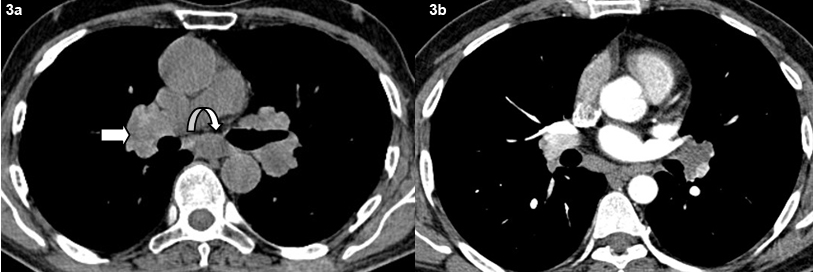

Axial non contrast (a) and contrast (b) CT images shows typical bilateral symmetrical hilar adenopathy (bold arrow) and subcarinal adenopathy (curved arrow).

A total of 29 patients had presence of mediatinal lymphdenopathy [Table/Fig-2]. Lymph nodes were present in the hilar, pre and paratracheal, AP window, prevascular and subcarinal regions. Bilateral hilar adenopathy was the most common finding seen in 22 patients [Table/Fig-3]. Paratracheal adenopathy especially on the right was seen in 15 patients. The size of the lymph nodes varied from 10 mm to 4.8 cm. Presence of conglomerate lymph nodes was seen in 11 patients. Necrosis present as low attenuating areas within the lymph nodes was not seen in any case. No retrocrural, internal mammary or significant axillary adenopathy was noted. A total of five patients had calcifications in the lymph nodes. Three patients had punctuate/nodular and two patients had egg shell calcification in the lymph nodes [Table/Fig-4].

Predominant involvement of hilar and right paratracheal lymph nodes is seen in 50-90% of the patients with mediastinal adenopathy in thoracic sarcoidosis [1,5–7]. The lymphadenopathy in sarcoidosis is usually non-necrotic, bilateral and symmetrical. Nodes are also seen in the prevascular region, AP window and subcarinal regions. In this study, 72.5% (n=29) of the patients had presence of mediastinal lymphadenopathy. Amongst them, 76% (n=22) had involvement of bilateral hilar lymph nodes and 15 patients in addition to hilar nodes had paratracheal lymphadenopathy. Patients also had nodes in the prevascular, sub aortic and subcarinal regions. Conglomerate lymph nodes were seen in 38% (n=11) patients. Nodal calcification is fairly frequent in long standing disease and the pattern can be amorphous, punctuate or eggshell [1]. Two patients (7%) had peripheral egg shell calcification in the hilar nodes. This finding has been reported in sarcoidosis although it may be seen in other conditions such as silicosis. The remaining three patients had a nodular/punctate pattern of calcification. Necrosis was not noted in the mediastinal nodes in this study. The characteristic predominant involvement of bilateral hilar and paratracheal lymph nodes associated with their typical non necrotic character, pattern of calcification and distribution found on HRCT in this study are in concurrence with findings of sarcoidosis in the published literature [8–10].